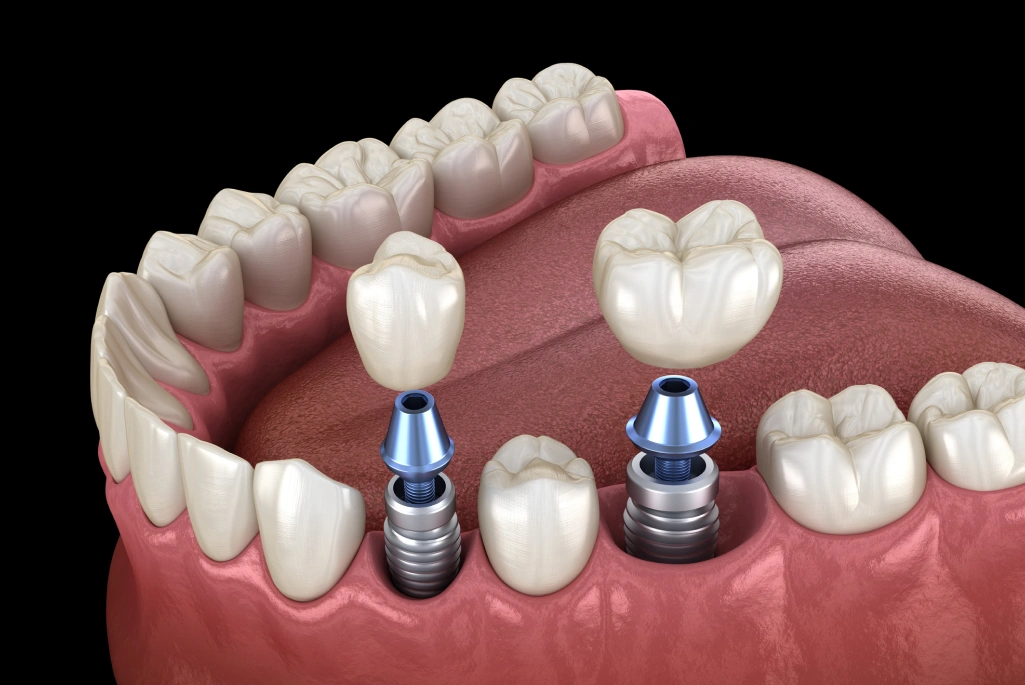

Dental Implants

There are many ways to replace teeth, but perhaps the most natural feeling and longest lasting option is a “man-made tooth” or Dental Implant.

Dental implants are a permanent solution for missing teeth, offering natural-looking results. They restore function, improve appearance, and support jaw health, helping you smile, chew, and speak with confidence.